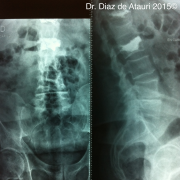

Puedes ver imágenes de una fractura y de la técnica quirúrgica de un caso real del 2015 tras este texto.